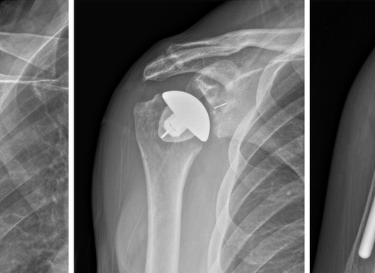

There are two primary types of shoulder replacements: anatomic and reverse. Anatomic shoulder replacement mirrors the shoulder's natural structure, while reverse shoulder replacement alters the joint mechanics to benefit patients with severe rotator cuff damage. The rationale for choosing either procedure often hinges on the patient’s specific condition, their anatomical needs, and overall health. As populations age and physical activity levels change, there has been a noticeable increase in the prevalence of shoulder replacements within orthopedic surgery practices. This rise reflects advancements in surgical techniques and artificial implant technologies, providing new options for those suffering from debilitating shoulder ailments.

Anatomic shoulder replacement, often utilized for patients with arthritis or trauma affecting the glenohumeral joint, involves replacing the damaged portions of the shoulder with implants that closely mimic the natural anatomy. The procedure typically utilizes a ball-and-socket implant system, wherein the humeral head is replaced with a prosthetic ball, while the socket (the glenoid) is lined with a polyethylene implant. The surgical technique requires precise alignment to ensure optimal shoulder mechanics, which allows for a more natural range of motion post-operation.

Conversely, reverse shoulder replacement is primarily indicated for patients with rotator cuff deficiency, severe arthritis, or failed prior shoulder surgeries. This procedure involves an inversion of the traditional implant design—here, the ball is attached to the shoulder socket, and a concave socket is placed on the upper arm bone (humerus). The reverse configuration redistributes the forces around the shoulder joint and employs different muscular dynamics, thus compensating for the lack of functional rotator cuff muscles. The surgical technique also necessitates careful consideration of patient anatomy, as the procedure aims to provide stability and improved range of motion in the affected joint.